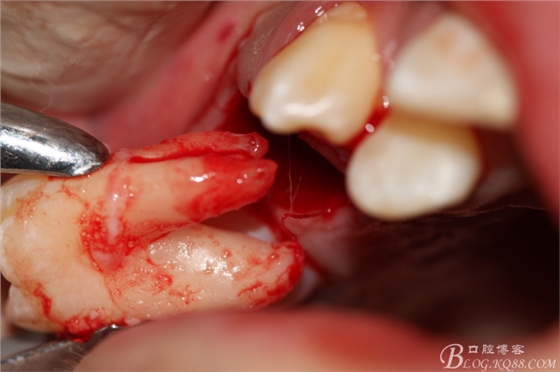

3.術(shù)中拔除上頜第一前磨牙照片